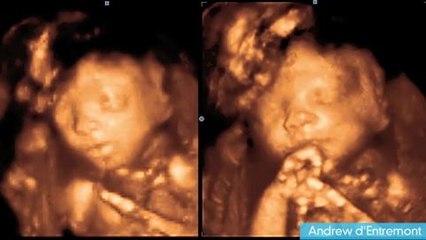

What to Expect at Week 9 | Week by Week Pregnancy Guidebr br The video is showing What to Expect at Week 9 but also try to cover the following subject:br -9th week of pregnancybr -9th week pregnancy symptomsbr -pregnancy week by weekbr br Youtube is the best place to go when looking for videos about What to Expect at Week 9.br What to Expect at Week 9 is certainly something that interests you and a lot of people so I made this video about this topic.